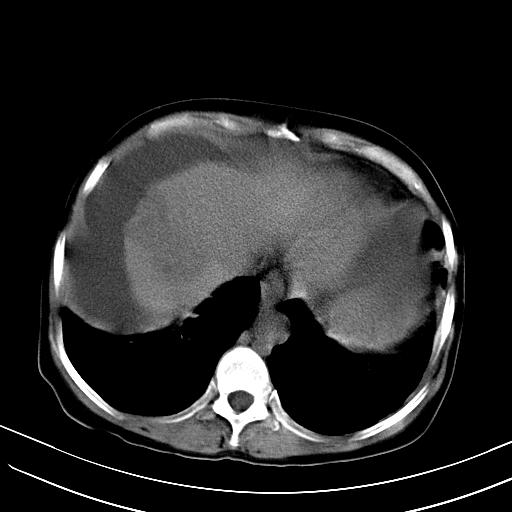

标题: CT23697:肝癌并肝动静脉漏? [打印本页]

标题: CT23697:肝癌并肝动静脉漏?

肝动静脉漏,动脉期肝动脉及门静脉内均可见造影剂……

1)肝右叶肝癌并肝动静脉漏。2)肝硬化,腹水。3)胆囊炎。

肝右叶肝癌并动静脉漏,肝硬化,腹水。

1)肝右叶肝癌并肝动静脉漏 门v右支瘤栓伴海绵样变。2)肝硬化,脾大 腹水。3)胆囊炎。门v高压.

右叶肝癌并肝动静脉漏(动脉期肝动脉及门静脉内均可见造影剂),肝硬化,腹水。(胆囊壁水肿)

1)肝右叶肝癌,考虑并发肝动静脉漏。扫描时间好像慢了。2)肝硬化,门脉高压、脾大、腹水。